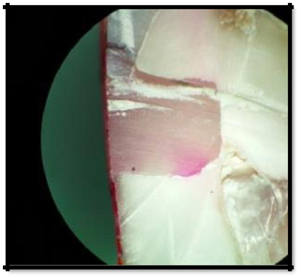

1. No leakage (Figure 4)

Figure 4 No Leakage (Score 0).